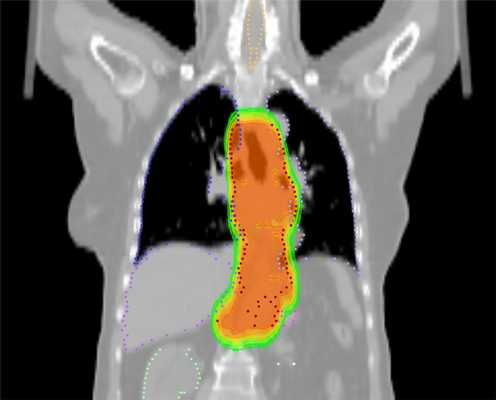

Принципиально иной подход предполагает применение инновационного метода лечения на аппарате Tomotherapy. Это устройство представляет собой облучатель, совмещенный с томографом, что позволяет максимально точно контурировать опухоль и не облучать окружающие ткани. Длительность лечения на аппарате составляет до полутора месяцев, а суммарно подводимая доза радиации — 40-50 Грей.